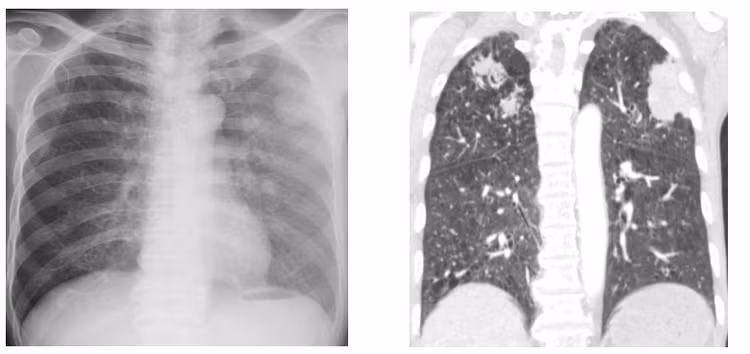

Các xét nghiệm cho thấy bệnh nhân có tình trạng thiếu máu mức độ trung bình, tăng bạch cầu ái toan (một trong những chỉ điểm của tình trạng nhiễm ký sinh trùng), viêm phổi với tổn thương dạng nốt lan tỏa hai phổi.

Bệnh nhân được chỉ định nội soi phế quản và nội soi dạ dày tá tràng để kiểm tra, ghi nhận tình trạng viêm dạ dày tá tràng có nhiều chấm trắng li ti gợi ý tình trạng nhiễm ký sinh trùng.

Khi các bác sĩ tiến hành nội soi phế quản cho bệnh nhân, bơm rửa ghi nhận được nhiều dị vật màu trắng xám, kiểm tra dưới kính hiển vi ghi nhận là ấu trùng giun lươn. Từ đó chẩn đoán của bệnh nhân được xác định là một tình trạng nhiễm giun lươn nặng ở phổi và ruột trên cơ địa suy giảm miễn dịch. Bệnh nhân được điều trị với thuốc đặc hiệu và xuất viện sau đó.